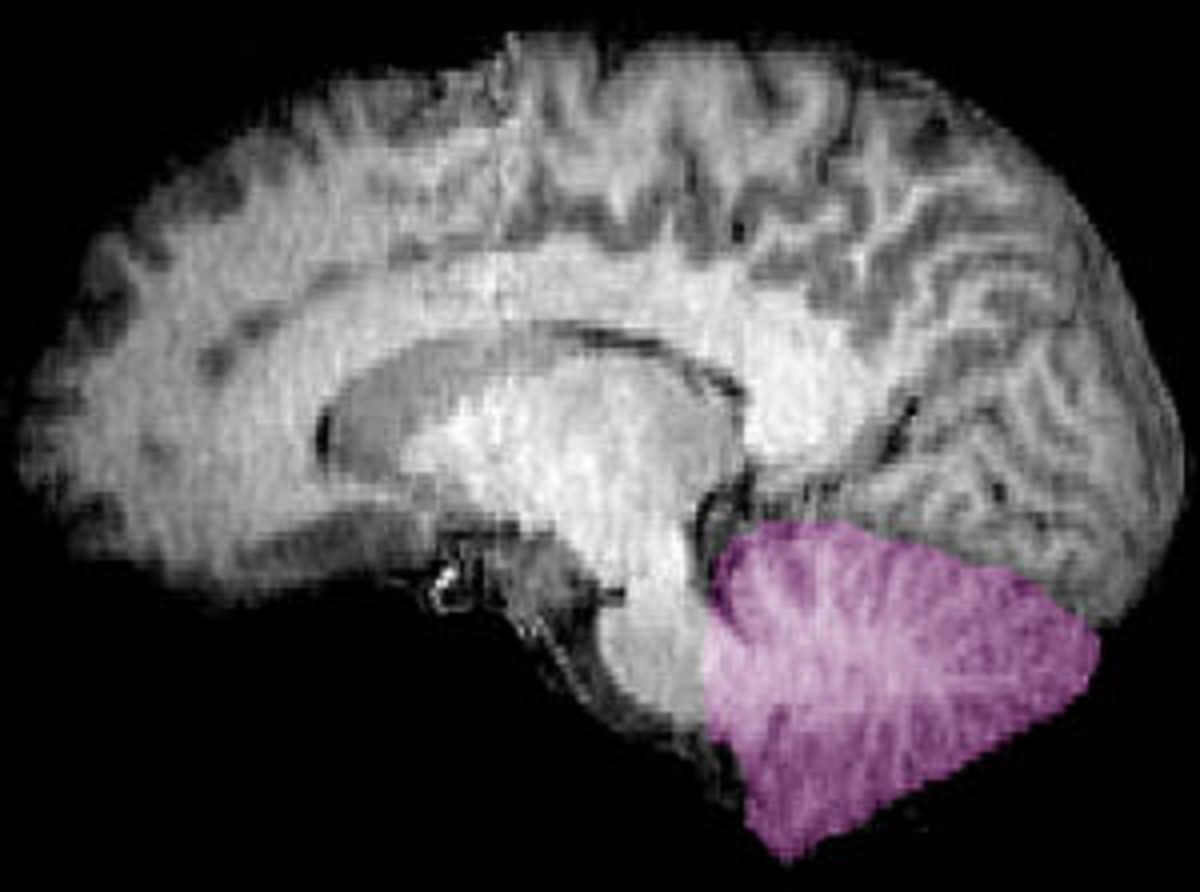

Imagen de resonancia magnética nuclear de una sección sagital de un encéfalo humano. Cerebelo en púrpura. Fuente: Wikipedia.

Sin embargo, la nueva investigación sugiere que otra región, conocida como cerebelo también estaría implicada pues, ha constatado el estudio, se ha ampliado “hasta seis veces más rápido de lo previsto a lo largo de la evolución, tanto de simios como de humanos”.

Uniendo este hallazgo al hecho de que el cerebelo de los seres humanos contiene cerca de 70 mil millones de neuronas -el 50% de las neuronas de todo el cerebro y cuatro veces más que el neocórtex- los investigadores han deducido que la inteligencia técnica “fue probablemente al menos tan importante como la inteligencia social en la evolución cognitiva humana”, señalan en un comunicado difundido por Eurekalert.

¿Por qué se relaciona el cerebelo con la inteligencia técnica? Pues porque la función principal de esta región, perteneciente al encéfalo, es la de integrar las vías sensitivas y las vías motoras (el cerebelo integra toda la información sensible que recibe para controlar las órdenes que la corteza cerebral manda al aparato locomotor). Por tanto, el cerebelo parece estar particularmente involucrado en la organización temporal de secuencias de comportamientos complejos, como los que participan en la fabricación y el uso de herramientas.